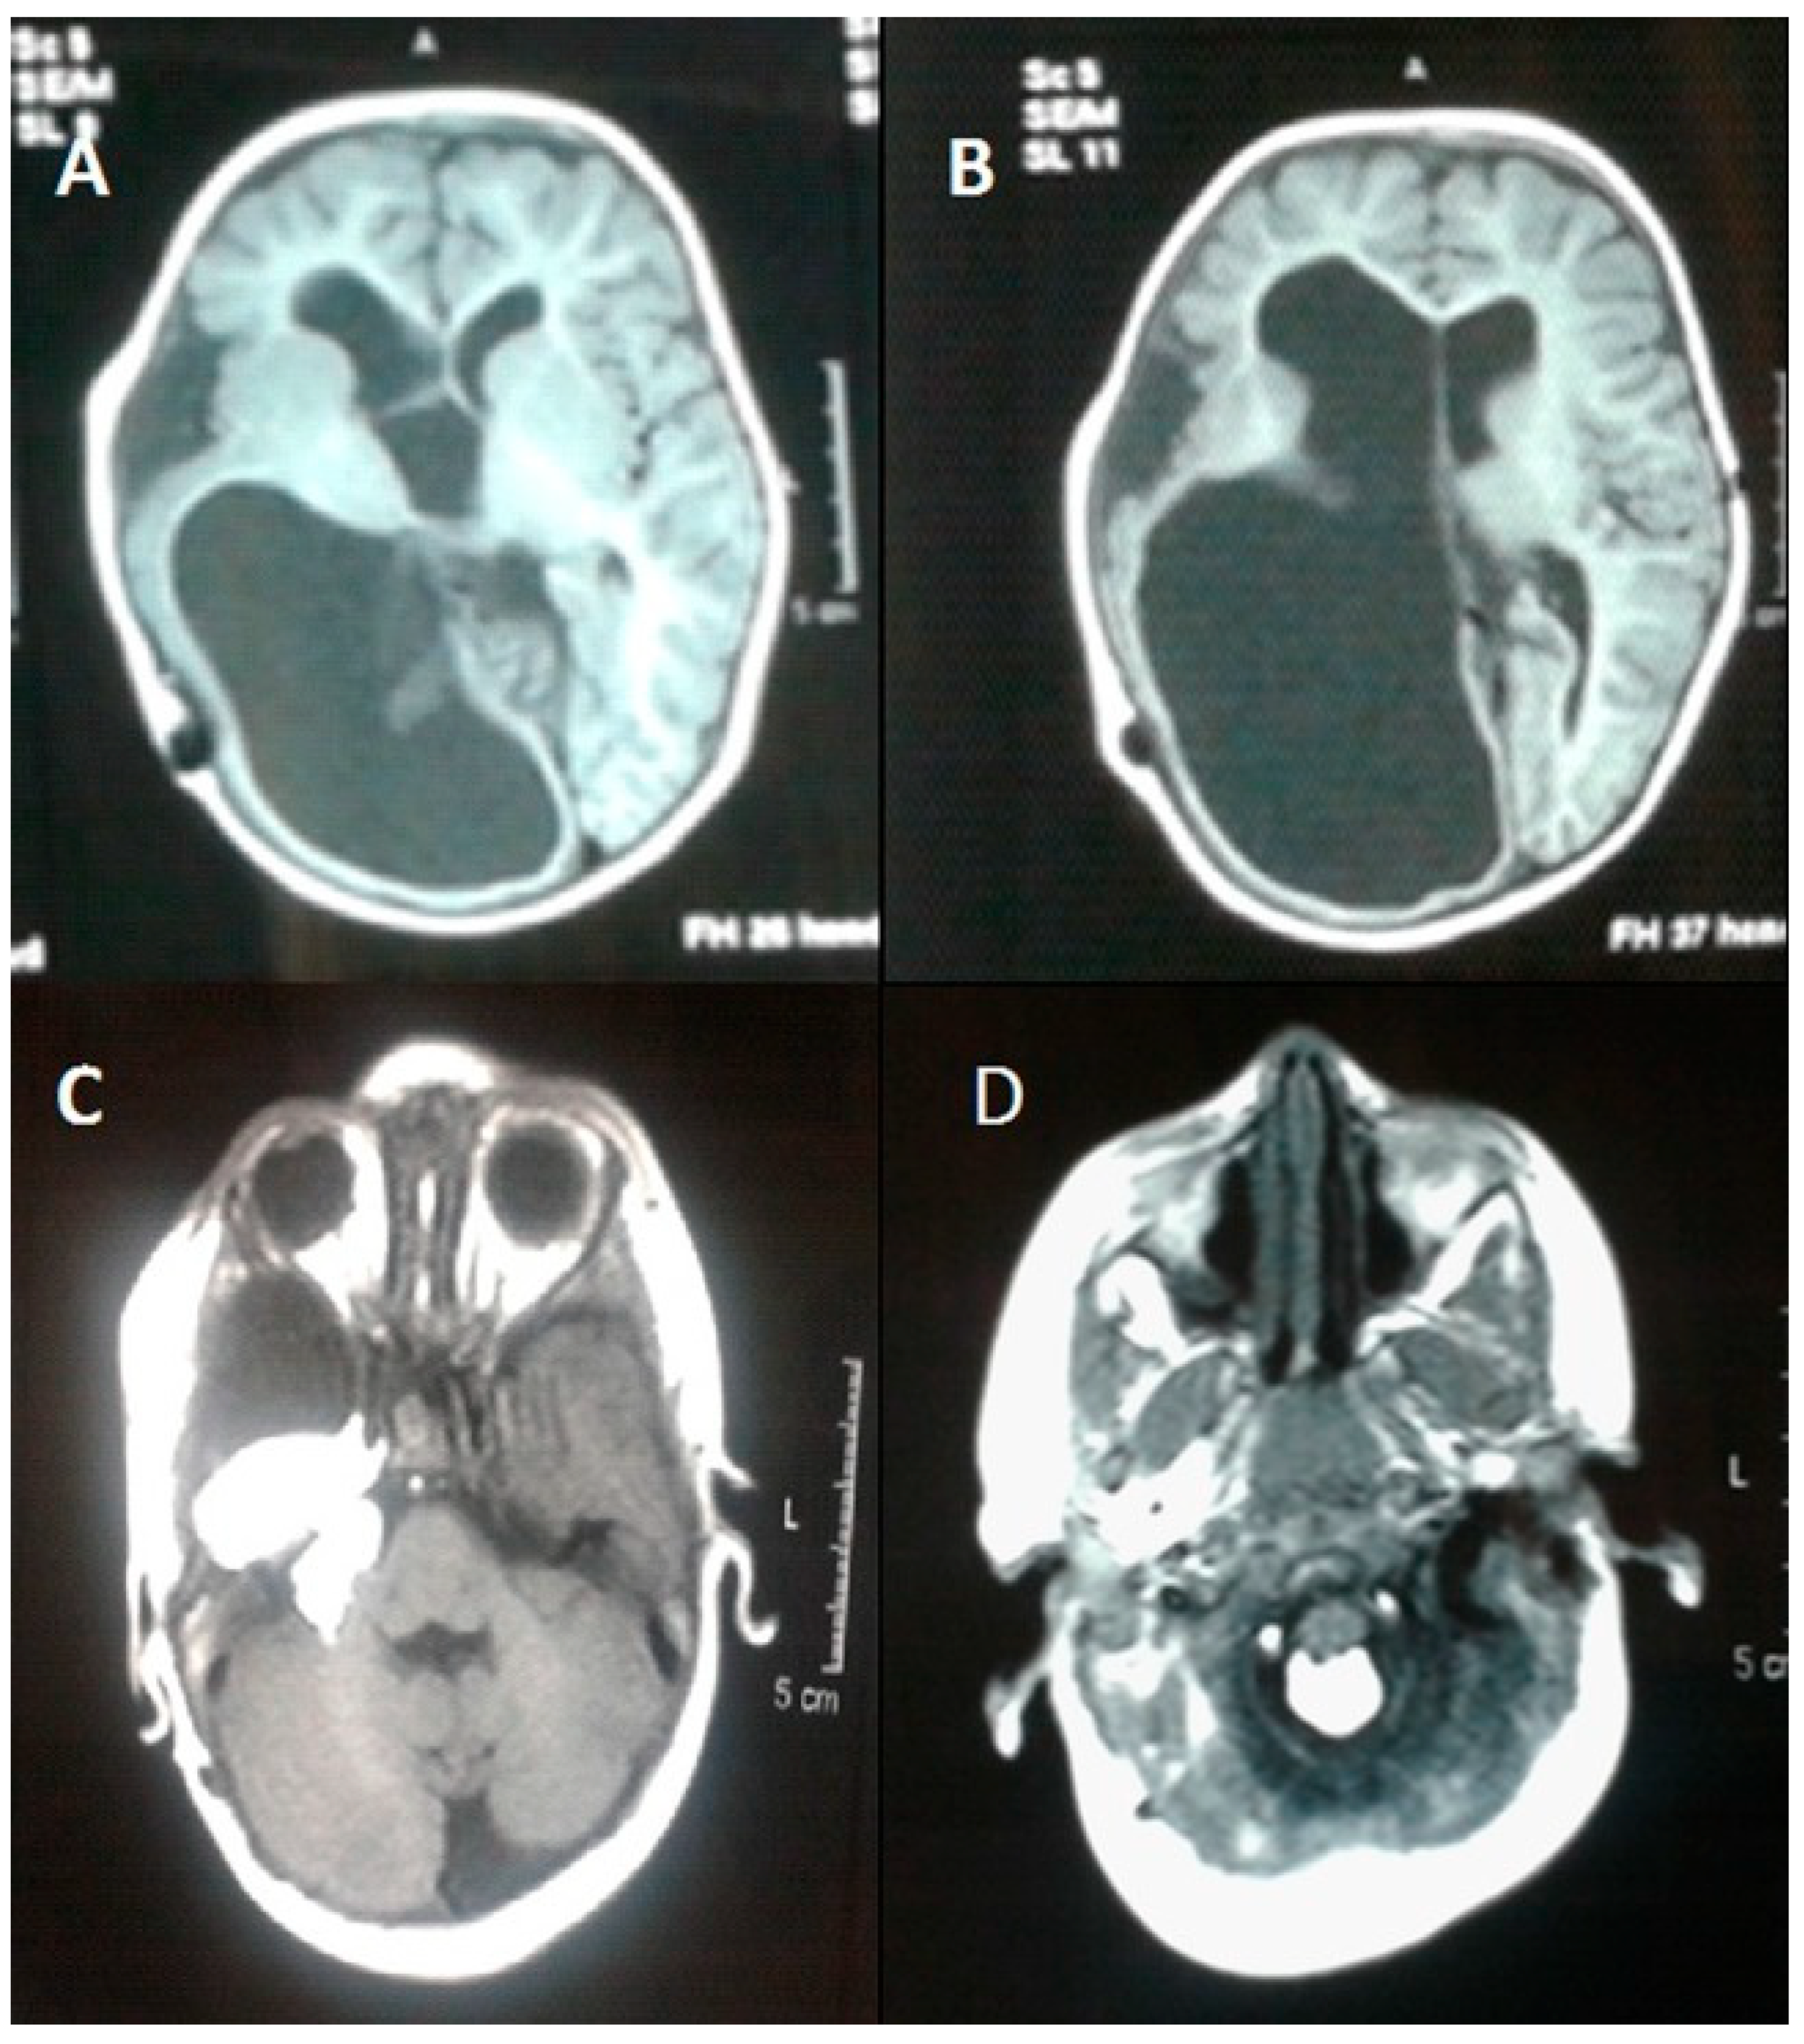

- Siddiqui, S.; Naaz, S.; Ahmad, M.; Khan, Z.A.; Wahab, S.; Rashid, B.A. Encephalocraniocutaneous lipomatosis: A case report with review of literature. Neuroradiol. J. 2017, 30, 578–582. [Google Scholar] [CrossRef] [PubMed]